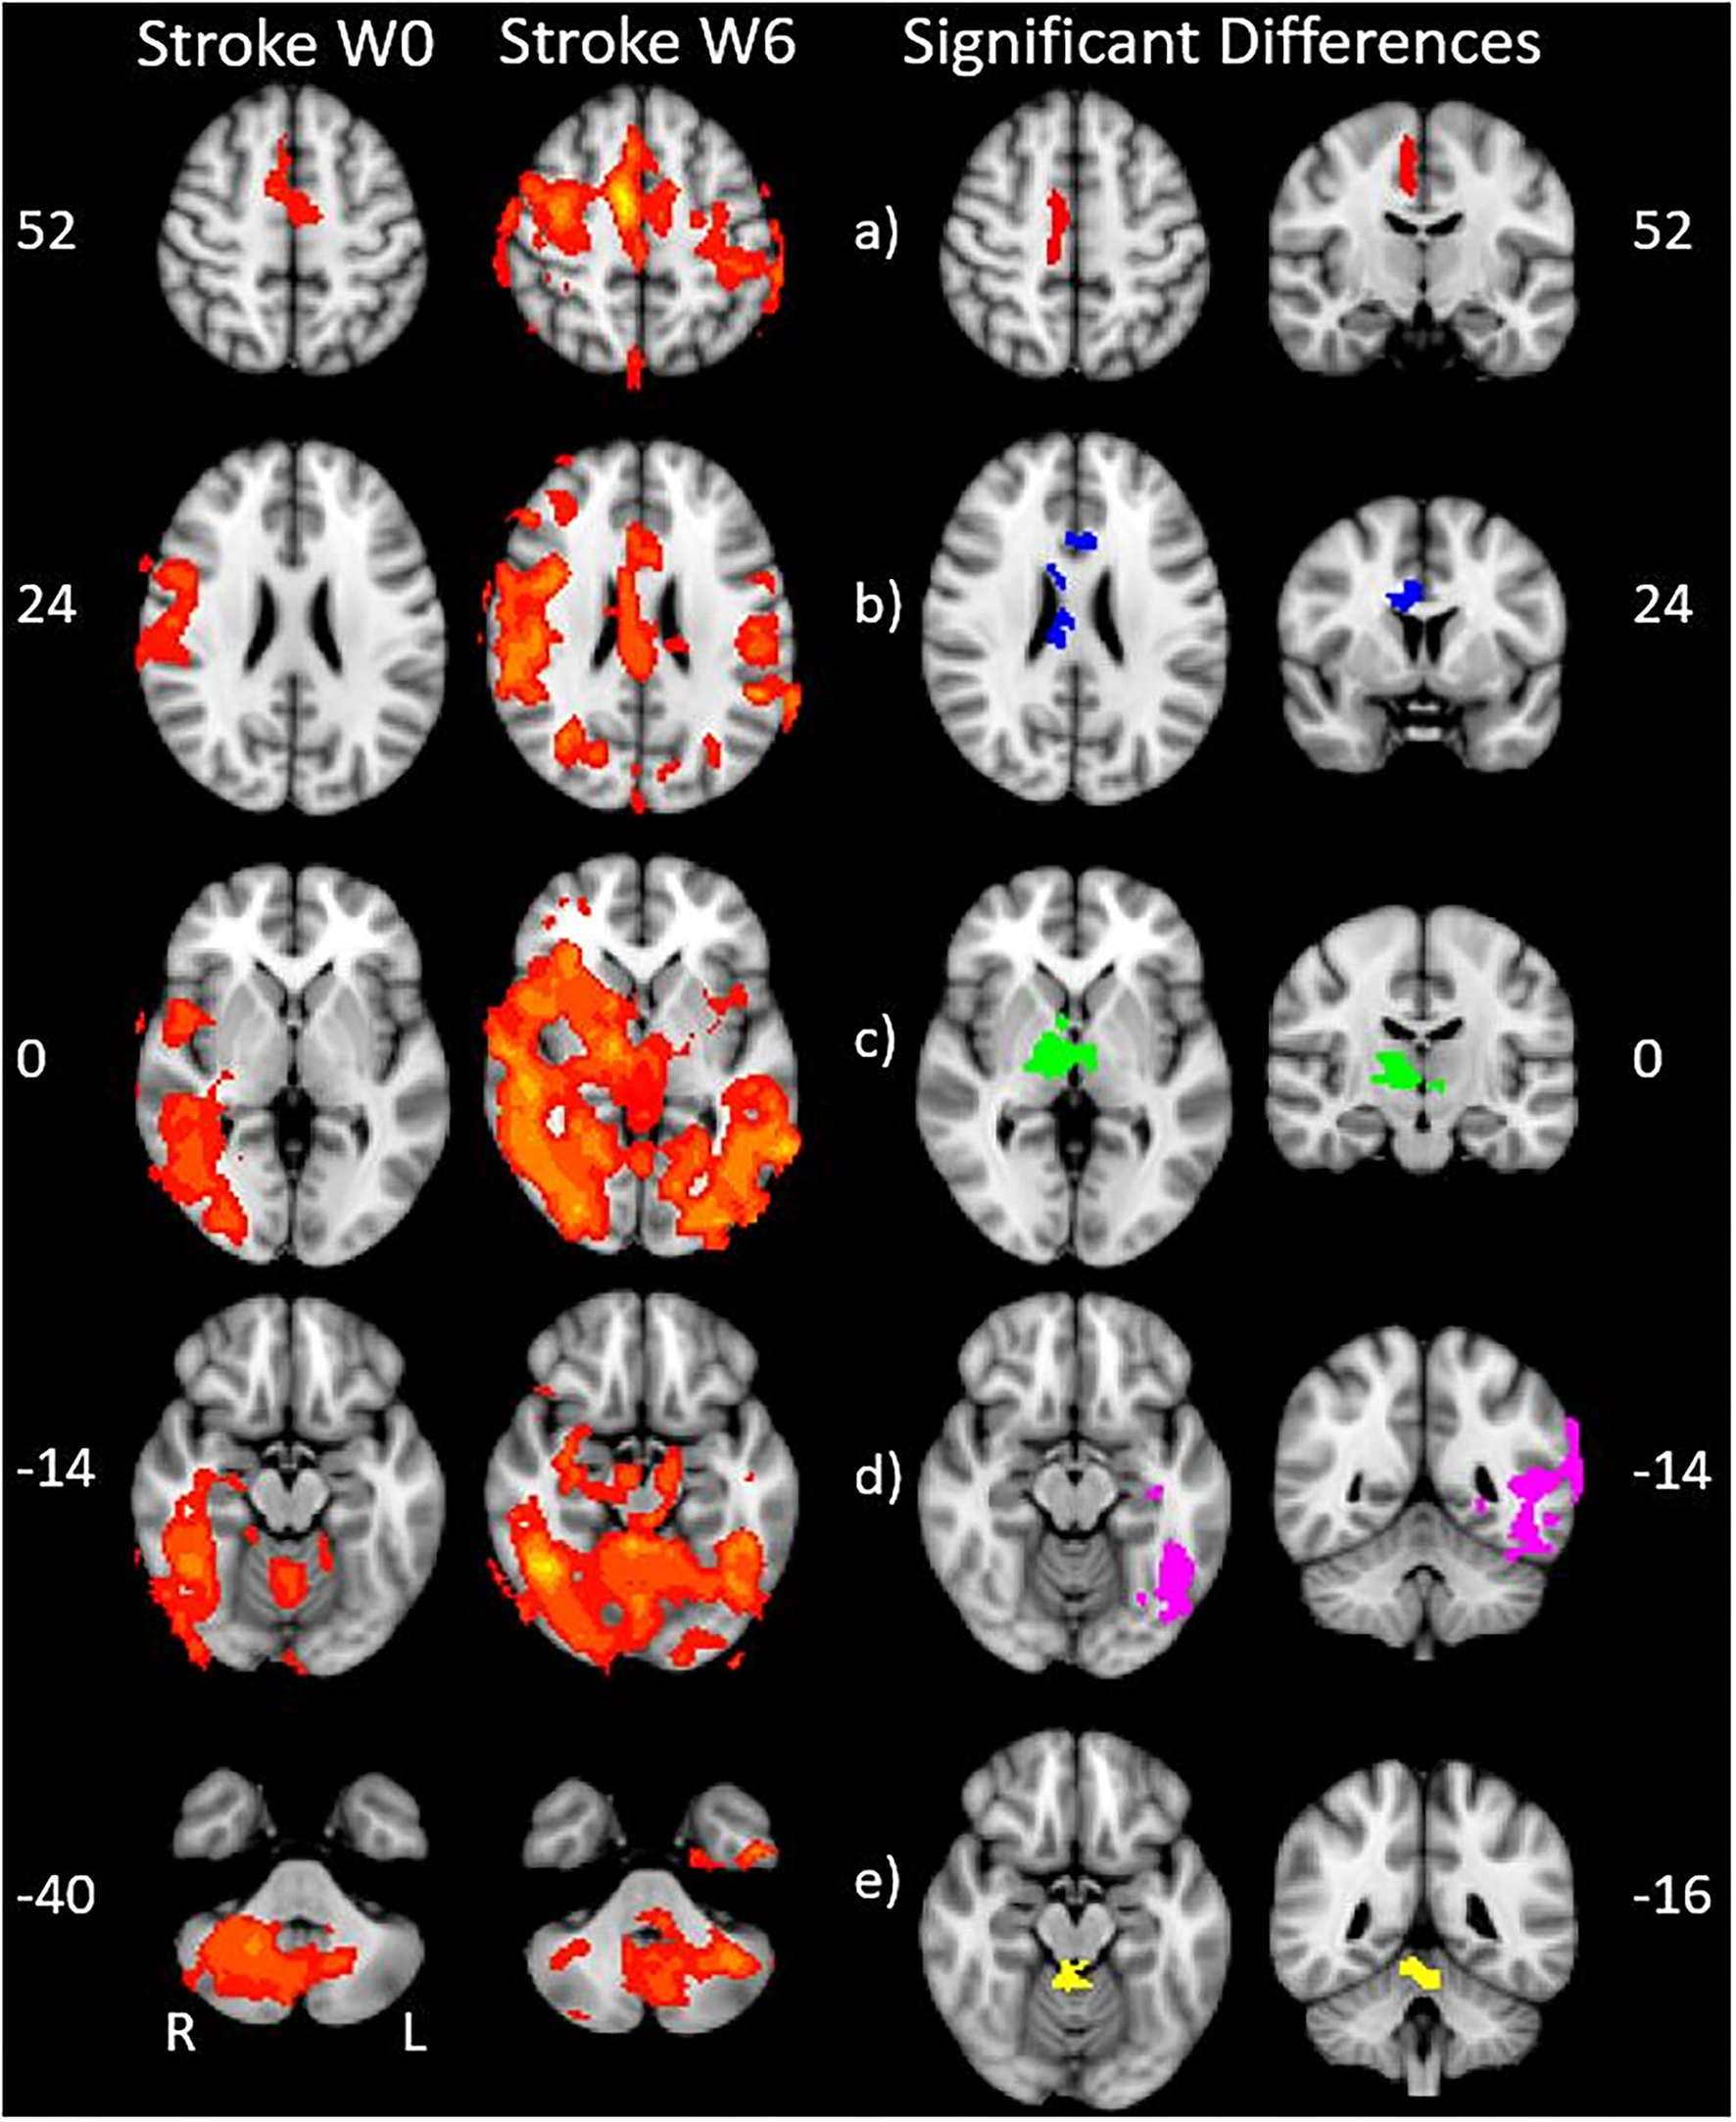

We found expected activity patterns and no significant difference between W0 and W6 sessions for controls. Across sessions, controls consistently and significantly activated bilateral primary motor (M1) and ipsilateral cerebellar areas at W0 and W6 (Figure 4) during right-hand movement. In addition to these regions, the ipsilateral premotor and supplementary motor area, bilateral hand portion of the M1, the thalamus and the putamen showed significant task-related activity. Although control participant's activity maps were similar across sessions, stroke participants showed differences between W0 and W6 (Figure 5). At W6 there was more widespread and bilateral activation in the stroke group compared with W0; whereas activation before injection was restricted to the contralesional hemisphere, activation increased in both hemispheres after injection (Figure 5). Activation maps yielded p-values for each voxel; these maps were threshold with p < 0.05 to assess significance. Significant differences (p < 0.05, df = 8; z > 2.3; paired z-test) between W6 and W0 in the stroke group included: (1) contralesional premotor cortex (PMC-R), (2) contralesional cingulate gyrus (CG-R), (3) contralesional thalamus (Th-R), (4) somatosensory and visual integration areas (Sens-IA), and (5) superior cerebellum (S-CB). These regions of activation are further described in Table 4 and illustrated in Figure 5.

Figure 5

Stroke differences during BoNT-A injections. The first two columns show significant (p < 0.05) levels of activity across the stroke group for W0 (left) and W6 (right). Columns 3 and 4 show the coronal (left) and axial (right) view of significant increase in activity following the BoNT-A intervention, displayed as five regions of interests. These areas are: (a) right premotor cortex (b) right cingulate gyrus (c) right thalamus (d) sensory integration area, (e) superior cerebellum. The physical coordinates of the axial slices are shown to the left or right of axial images, and the coronal views are denoted by the yellow horizontal lines.